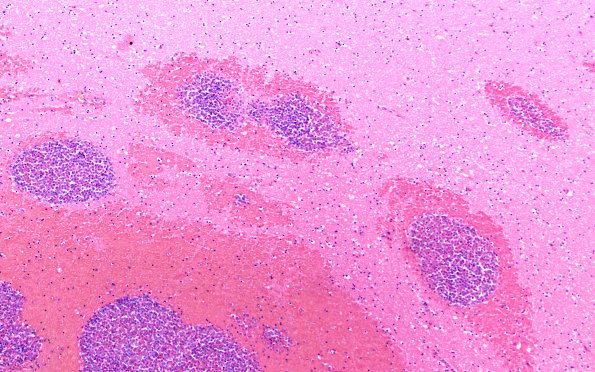

Washington University Experience | NEOPLASMS (HEMATOLYMPHOID) | Granulocytic Sarcoma | 3B3 Leukemic Nodules (Case 3) 10X 1

Higher magnification images of the nodule of image #3B1 demonstrating its myeloblastic center. Surrounding neural tissue showed acute white matter edema with ameboid glia and some karyorrhexis adjacent to the nodules (H&E)